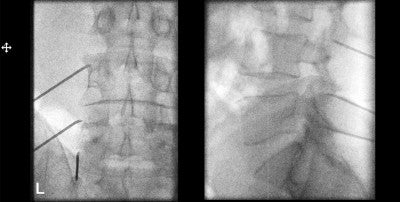

After injecting local anesthetic under fluoroscopic guidance, pain management specialists assess the extent of the person’s pain relief from the block, which typically lasts around six hours.

“If pain is coming from those facet joints, we expect a significant improvement in the patient’s pain when they’re numbed up by the medial branch block,” Grimaldi says.